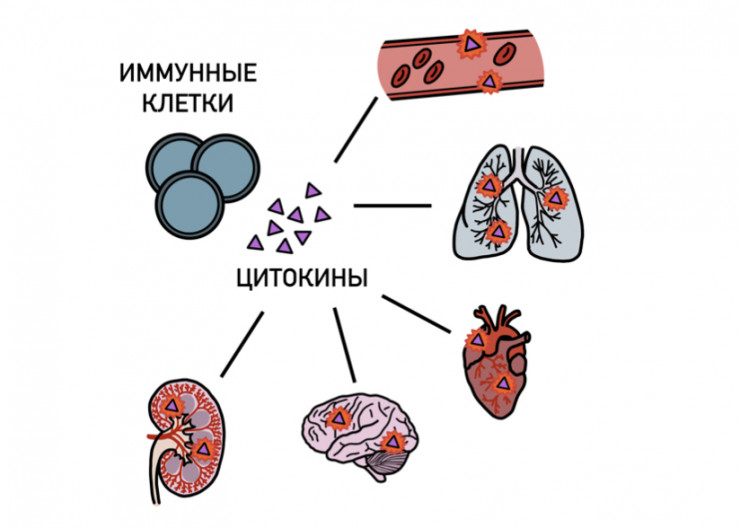

Одним из механизмов развития COVID-19 является так называемый цитокиновый шторм. Он связан с тем, что система иммунной защиты вырабатывает огромные количества молекул, называемых цитокинами. Они вызывают многочисленные нарушения в организме. Поведение иммунной системы во время цитокинового шторма напоминает заклинивание газовой педали автомобиля, из-за чего он сильно разгоняется, теряя способность остановиться, и может вести к катастрофе.

Цитокиновый шторм наблюдается далеко не у всех пациентов с COVID-19, но если он развивается, то его следует ожидать на 10-е сутки после заражения. Большую опасность представляет дыхательная недостаточность, из-за которой иногда приходится идти на крайнюю меру – использовать аппарат искусственного дыхания – ИВЛ. Важно не доводить до этого. Также наблюдается воспаление сердечной мышцы, головного мозга, почек, поджелудочной железы и многих других органов.

Таким образом, ответ организма на коронавирус может быть таким же разрушительным, как и сам коронавирус. То есть при COVID-19 важно не только бороться с вирусом, но и сдерживать ответ на него организма.

У трети больных с тяжелой формой COVID-19 цитокиновый шторм вызывает снижение тонуса сосудов, повышение их проницаемости, отеки и сгущение крови. Все это может вести к образованию опасных тромбов. Для борьбы с ними применяют так называемые антикоагулянты. В маленьких дозах антикоагулянты можно использовать и после выписки из больницы.